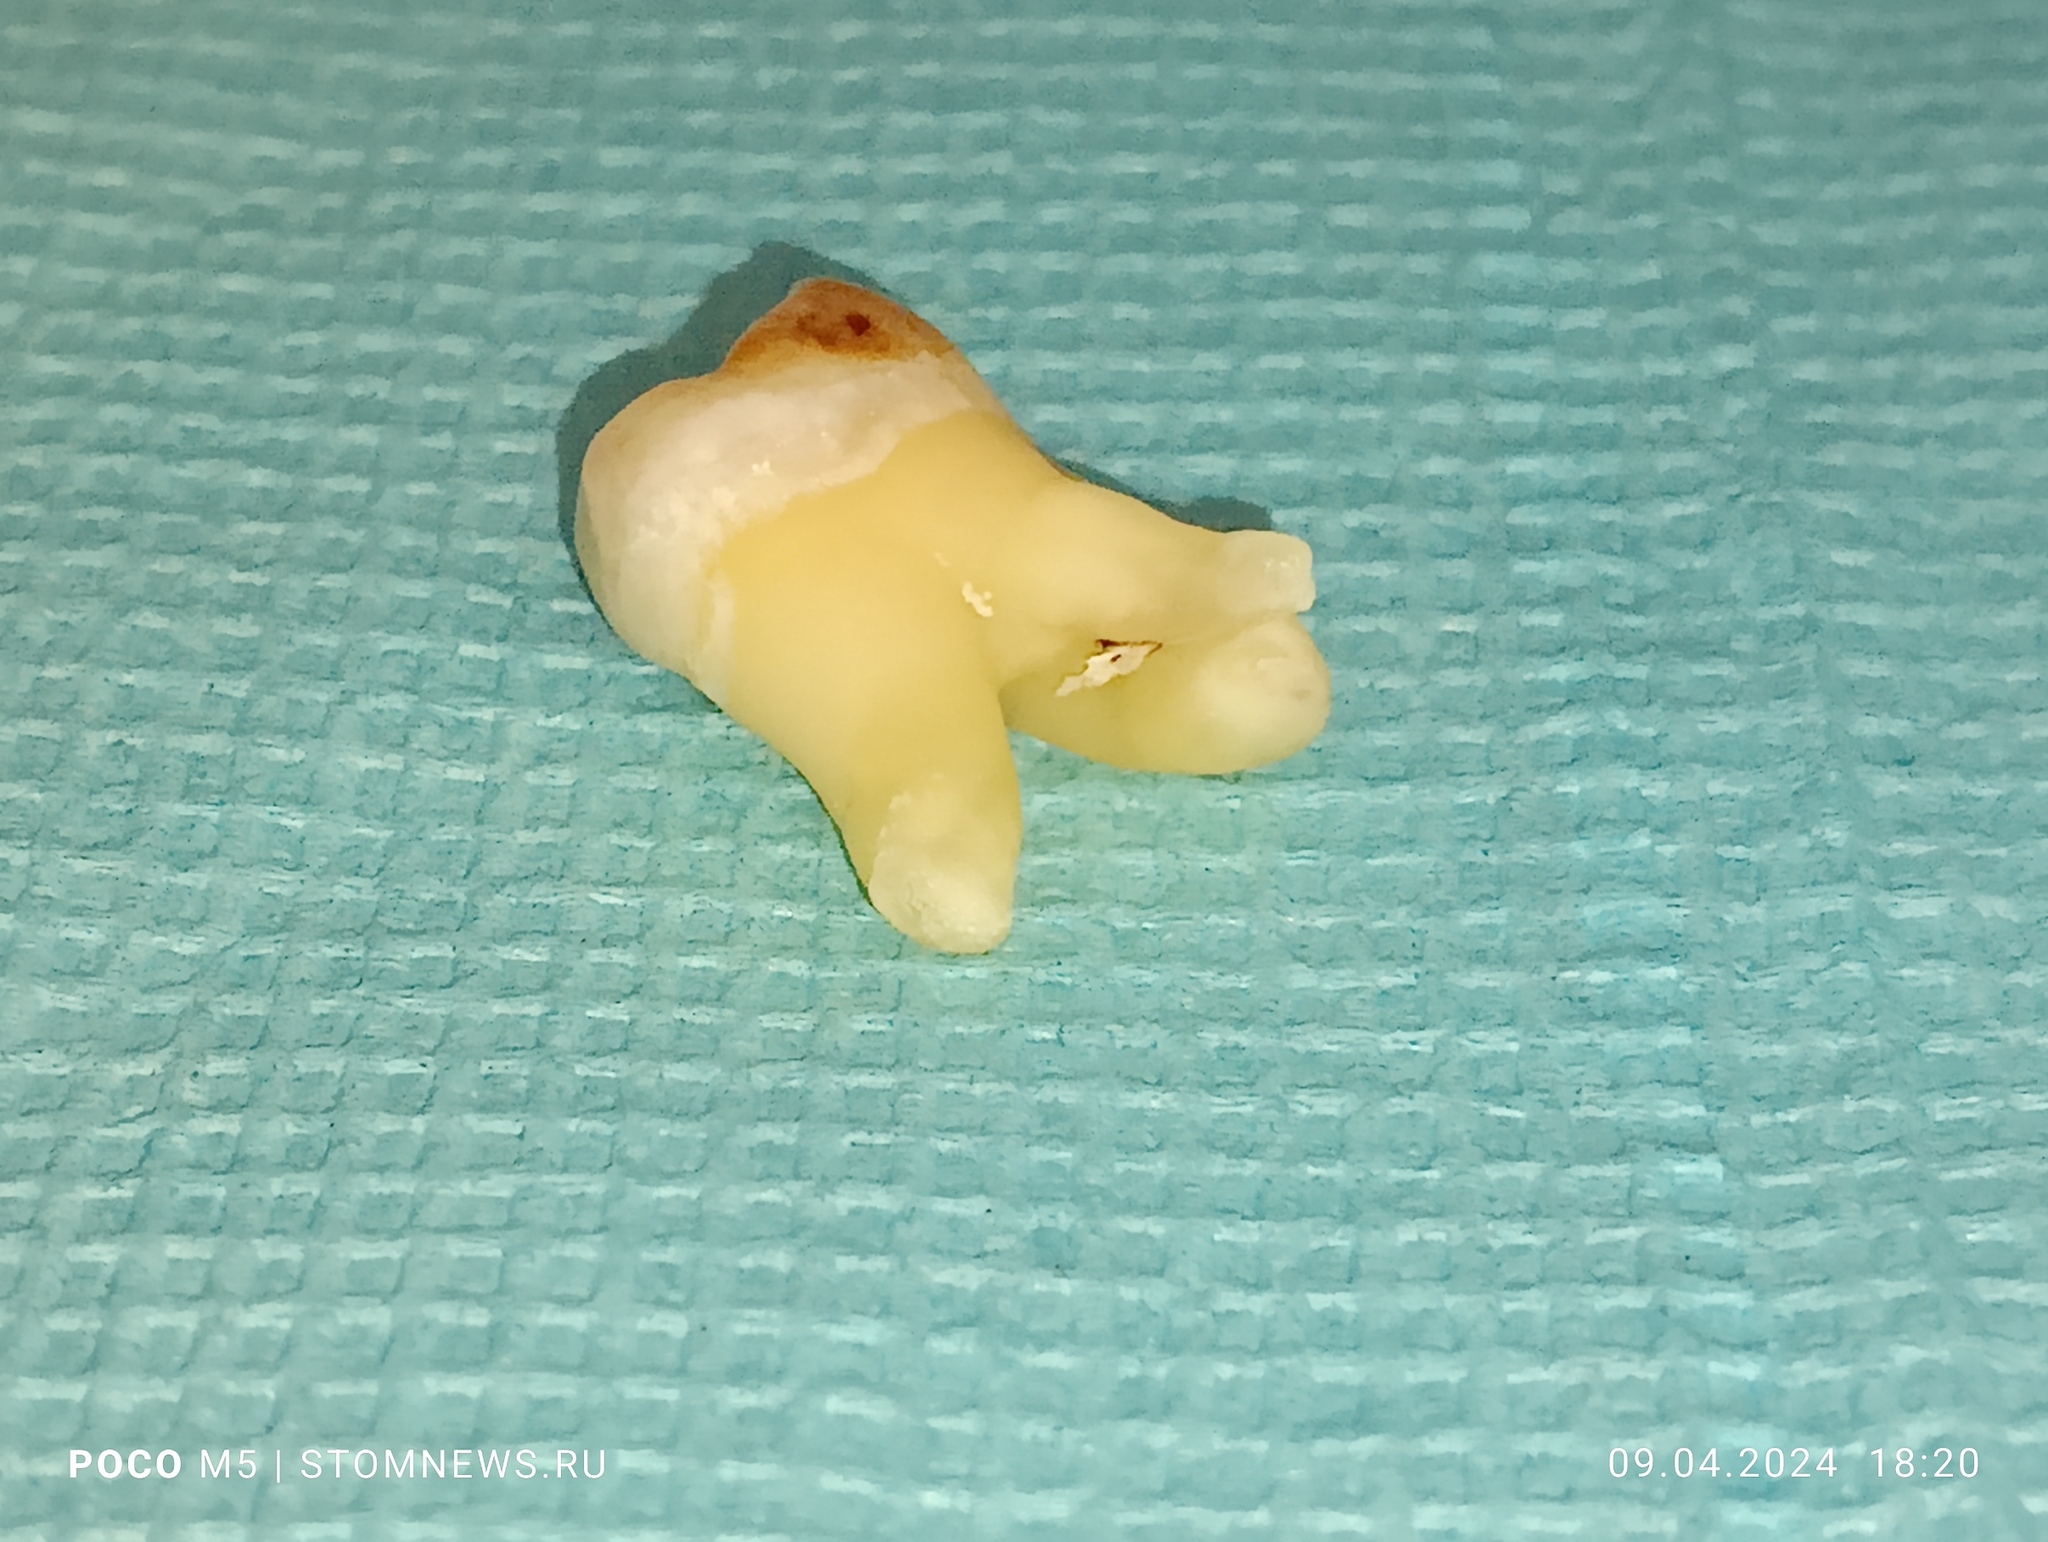

Удаленный 28 зуб мудрости с корнями по типу «оленьи рога»

💥Вот такой клинический случай произошел у меня на приеме сегодня: 09.04.20024 💥

😬Как оказалось, у пациента слева вверху запряталась восьмерка, которая только не давно прорезалась. При пальпации слизистой в области 28 зуба пациент резко дёргался 😱😱😱

☄️Было принято решение об удалении, так как спасти его не представлялось возможным👊

✌️Я решил сделать серию фотографий и выложил их на свой собственный сайт в виде галереи. Если вам интересно посмотреть поближе на этого монстра, то переходите по ссылке ниже👇👇👇